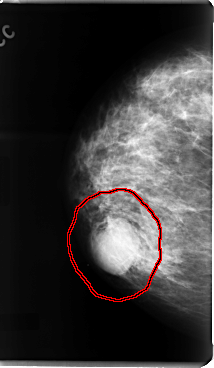

C_0076_1.RIGHT_MLO

RIGHT_MLO LINES 4784 PIXELS_PER_LINE 2832 BITS_PER_PIXEL 12 RESOLUTION 50 OVERLAY

FILE: C_0076_1.RIGHT_MLO.OVERLAY

TOTAL_ABNORMALITIES 1

ABNORMALITY 1

LESION_TYPE MASS SHAPE LOBULATED MARGINS MICROLOBULATED

ASSESSMENT 4

SUBTLETY 5

PATHOLOGY MALIGNANT

TOTAL_OUTLINES 1

BOUNDARY